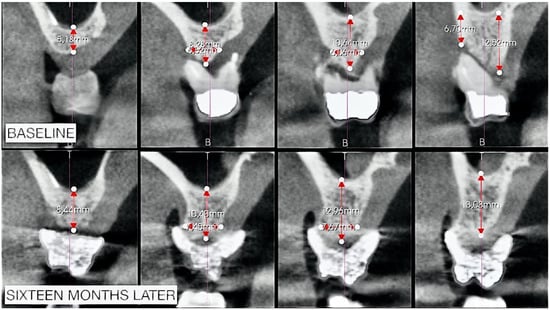

2.2. Radiographic Observations